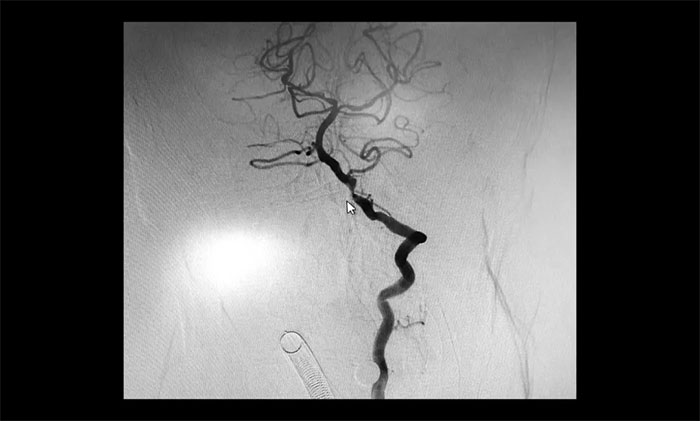

術(shù)后康復(fù)觀察一月余,于耀宇主任團(tuán)隊(duì)再次為曹老伯行右側(cè)頸動(dòng)脈支架置入及左側(cè)椎動(dòng)脈支架置入手術(shù)。術(shù)中造影顯示,右側(cè)頸內(nèi)動(dòng)脈起始段重度狹窄,狹窄長(zhǎng)度8mm左右。左側(cè)椎動(dòng)脈 V4 段重度狹窄,長(zhǎng)度6mm左右。運(yùn)用嫻熟扎實(shí)的技術(shù),在充分做好腦保護(hù)的前提下經(jīng)過(guò)多次球囊擴(kuò)張后,順利釋放支架于狹窄處。造影提示支架打開(kāi)良好,血管狹窄基本恢復(fù)正常,支架貼壁佳,支架內(nèi)血流通暢,遠(yuǎn)端血流良好。

▲ 術(shù)后,右側(cè)頸內(nèi)動(dòng)脈及左側(cè)椎動(dòng)脈狹窄明顯改善